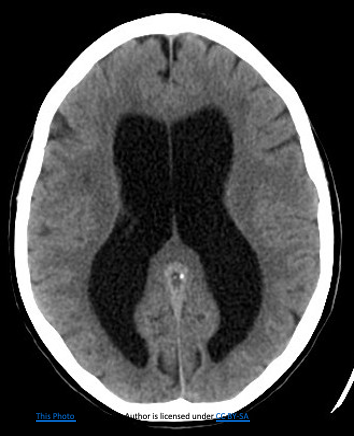

Raised  ICT